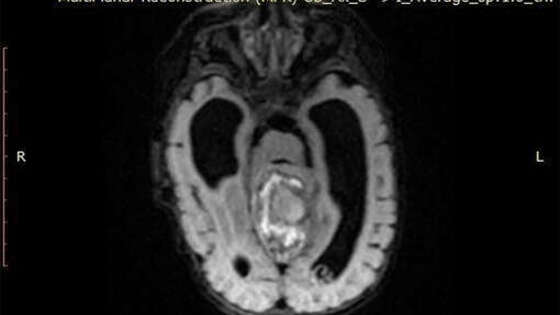

В детской республиканской больнице Башкирии хирурги удалили злокачественную опухоль мозга двухмесячному младенцу. Об этом сообщает пресс-служба Минздрава республики. Ребенок был доставлен в республиканскую больницу Уфы бортом санавиации, состояние младенца стремительно ухудшалось, у маленького пациента наблюдалась частая рвота, голова ребенка увеличилась в размерах. В ходе обследования медики обнаружили у младенца опухоль головного мозга, новообразование удалось успешно удалить. Гистологический анализ показал, что опухоль была злокачественной, было принято решение продолжить лечение ребенка в федеральном центре, пациента перевели в Москву, где ему оказывается вся необходимая медицинская помощь.